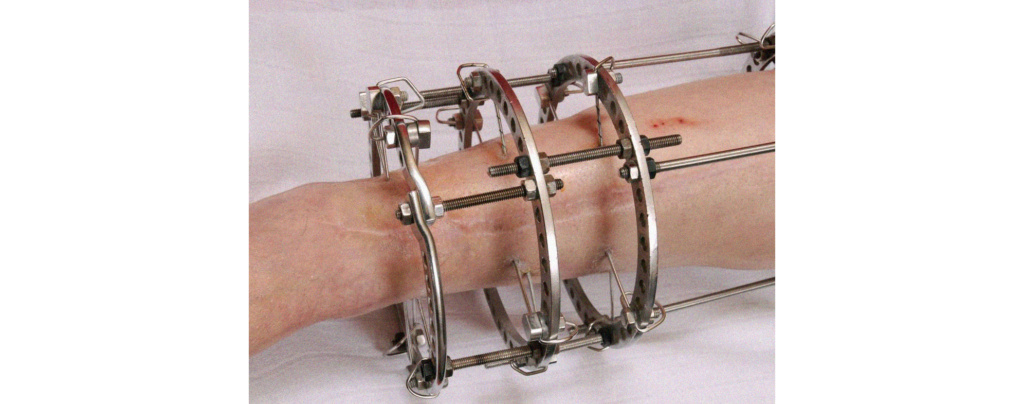

Аппарат Илизарова: принцип работы и применение

Раздел: Моменты озарения